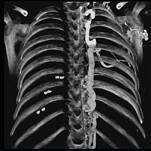

问题 下面一组图像显示的是 ( )

选项 A、奇静脉增粗可见于各种病因引起的上腔静脉梗阻 B、奇静脉增粗可见于各种病因引起的下腔静脉梗阻 C、正常的奇静脉干直径小于1.0cm D、奇静脉弓层面其直径小于1.2cm E、奇静脉扩张

答案 ACDE